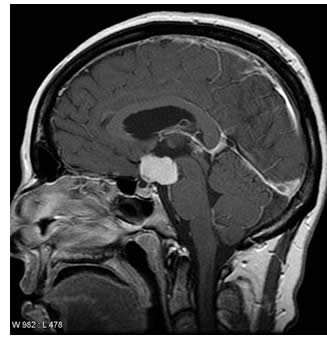

Niccolò dall’età di 8 anni convive con un craniofaringioma, tumore cerebrale solitamente benigno, che si origina in alcune cellule particolari situate in prossimità dell’ipofisi, le cause sono ancora sconosciute. Questo tumore può presentare diversi disturbi tra cui: mal di testa, nausea, vomito, problemi visivi e disturbi legati all’alterazione dei livelli ormonali ipofisari.

Craniofaringioma